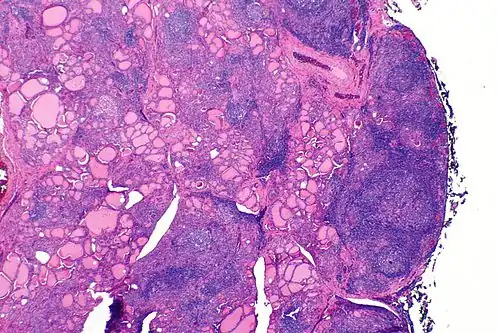

A micrograph of the thyroid of someone with Hashimoto's thyroiditis

Marked lymphocytic infiltration (purple areas) of the thyroid gland in a patient with chronic autoimmune thyroiditis

High powered magnification showing lymphocytic infiltration of the thyroid gland in autoimmune thyroiditis

Gross pathology of a thyroid with autoimmune thyroiditis may show a symmetrically enlarged thyroid.[5] It is often paler in color, in comparison to normal thyroid tissue, which is reddish-brown.[5]

Microscopic examination (histology) will show lymphocytes (including plasma B-cells) diffusely infiltrating the parenchyma.[55] The lymphocytes are predominately T-lymphocytes with a representation of both CD4+ and CD8+ cells.[5] The plasma cells are polyclonal, with present germinal centers resembling the structure of a lymph node[5] (also called secondary lymphoid follicles, not to be confused with the normally present colloid-filled follicles that constitute the thyroid).[55]

In late stages of the disease, the thyroid may be atrophic.[10] Colloid-filled follicles shrink, and the cuboidal cells that usually line the follicles become Hürthle cells.[5] Fibrous tissue may be found throughout the affected thyroid as well.[5] Severe thyroid atrophy presents often with denser fibrotic bands of collagen that remain within the confines of the thyroid capsule.[55]

Generally, pathological findings of the thyroid are related to the amount of remaining thyroid function — the more infiltration and fibrosis, the less likely a patient will have normal thyroid function.[5] A rare but serious complication is thyroid lymphoma, generally the B-cell type, non-Hodgkin lymphoma.[24]